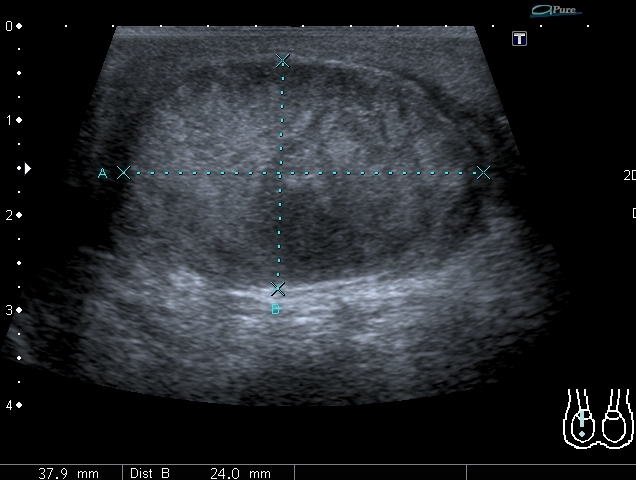

В приёмный покой больницы поступил мальчик 14 лет с жалобами на отёк правой половины мошонки и боли в правом яичке. При УЗИ - правое яичко увеличено отностиельно левого, изменено по структуре, расположено выше левого.